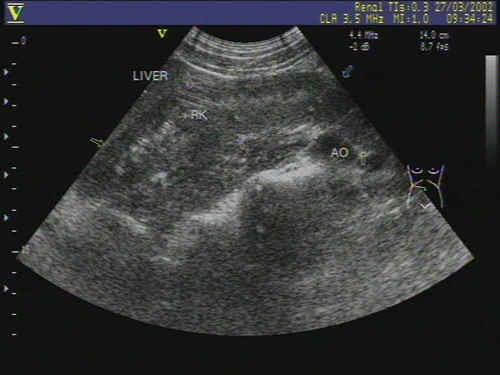

肾先天性反常--融合肾? - 超声医学讨论版 - 爱爱医医学论坛

图片尺寸640x480